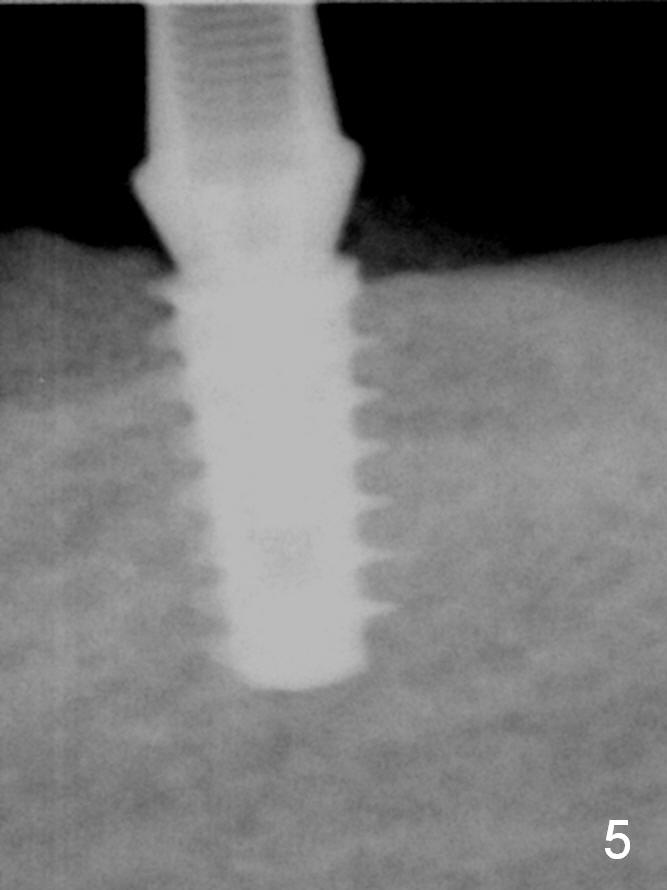

All of the 5 implants shown above are ~ 5 mm in diameter, placed in the lower 1st molar site. The first implant system used in my office is press fit (Fig.1). The reason to switch is its inability for immediate implant. The tissue-level implant appears to have aggressive thread patterns (Fig.2, bone/Titanium ratio: 50/50). To improve cosmetics, a bone-level implant is used (Fig.3). To enhance primary stability, a better thread patterned implant is chosen (Fig.4, bone/Titanium ratio: 70/30). It is apparent that IBS implant has the sharpest threads (fins, bone/Titanium ratio: 90/10, Fig.5)). It is consistent with my clinical cases. All of the implants mentioned above are placed at the site of #19 with diameter 4.5-6 mm and length 8-17 mm.